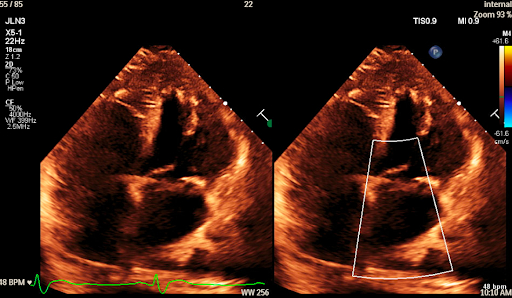

A 70-year-old female with coronary artery disease post-CABG, SLE with prior lupus nephritis and kidney transplant, and recurrent DVTs presented with dyspnea and bilateral leg edema. Her labs revealed macrocytic anemia, elevated NT-proBNP (41,167 pg/mL), and HS troponin-I (peak 689 ng/L). EKG showed sinus bradycardia, right bundle branch block, and low-voltage QRS complexes (Figure 1). Echocardiography demonstrated preserved ejection fraction of 55%, mild concentric LVH, and biatrial enlargement (Figure 2). Coronary angiography showed a mid-RCA lesion treated with PCI, but her symptoms persisted. The discordance between a low-voltage EKG and increased wall thickness on echocardiography raised suspicion of infiltrative cardiomyopathy. Serum and urine immunofixation and light chain analysis ruled out AL amyloidosis. A technetium-99m PYP scan showed grade 3 uptake with a heart-to-contralateral ratio of 1.52 (Figure 3). Genetic testing ruled out TTR mutation, confirming wild-type ATTR-CM. She was treated with cautious diuresis using lasix and referred for outpatient disease-modifying treatment.